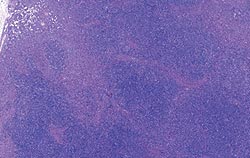

| Allure normale | Légère perturbation de l’architecture folliculaire |

| Perturbation modérée de l’architecture folliculaire | Perturbation intense de l’architecture folliculaire |

Déplétion lymphocytaire et infiltration granulomateuse légères, modérées et intenses comparées à un ganglion de structure histologique normale. Les lésions modérées et intenses sont indicatrices de la MAP. Coloration HE.